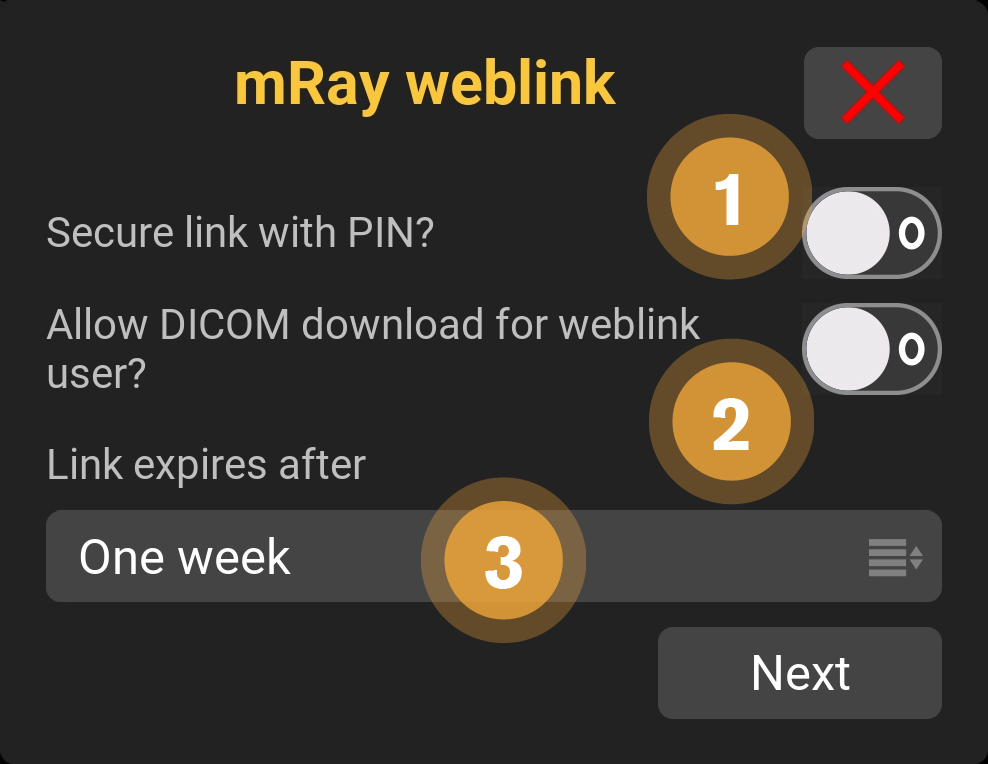

9.14. Link Settings

Various options are available when sharing content via links.

-

Choose if the recipient can download the content.

-

Allow the recipient to download the shared DICOM data.

-

Select when the link should expire. The content is visible for the recipient up to 6 months.